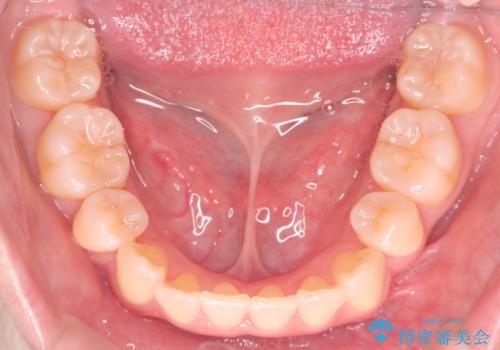

- 前歯が出ていることと、下の歯のがたがたで歯磨きがしにくいことを主訴に来院されました。

来院が途中途絶えたこともあり、4年ぐらい期間がかかりましたが、インビザラインだけで治療を終えることができました。